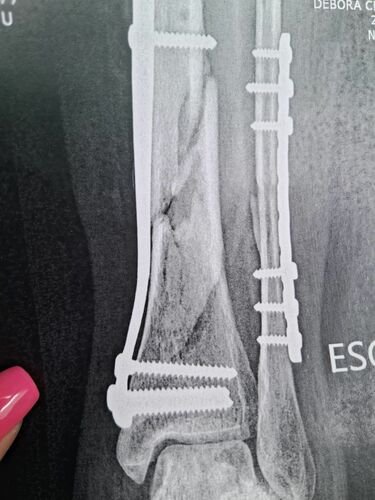

Sou a Jaqueline, criei essa vaquinha para arrecadar dinheiro para cirurgia da minha irmã Debora Cristina Luebke, que sofreu um acidente de moto no dia 07 de março de 2024. Desde então já passou por três cirurgias, e ainda não se recuperou. Medico nos informou que ela precisara passar por uma quarta cirurgia, que seria um tratamento cirúrgico pseudoartrose tíbia (A pseudoartrose é uma complicação que ocorre quando o osso não se consolida após uma fratura.) porem o valor ficou de R$ 19.710,00. A cirurgia seria com um enxerto sintético para colocar na tíbia e, seria menos invasiva e não deixaria com sequelas, com recuperação de 3 meses. Se formos esperar para fazer pelo SUS, seria feito outro tipo de cirurgia, no qual ela precisaria tirar um osso do corpo dela e colocar na tíbia e, ainda assim, ela poderia ficar com sequelas, ficando com uma perna maior que a outra, tendo que colocar a parabolica e sem previsão de quando o osso irá calcificar. Se isso acontecer, o trabalho dela que hoje em dia é de vigilante, ela não poderá mais atuar. Por isso venho por meio dessa vaquinha, pedir a ajuda de todos, qualquer valor é bem-vindo! Temos 30 dias para arrecadar esse valor estamos correndo contra o tempo. Conta no nome de Jaqueline CHAVE PIX EMAIL: deboracristinaluebke@gmail.com